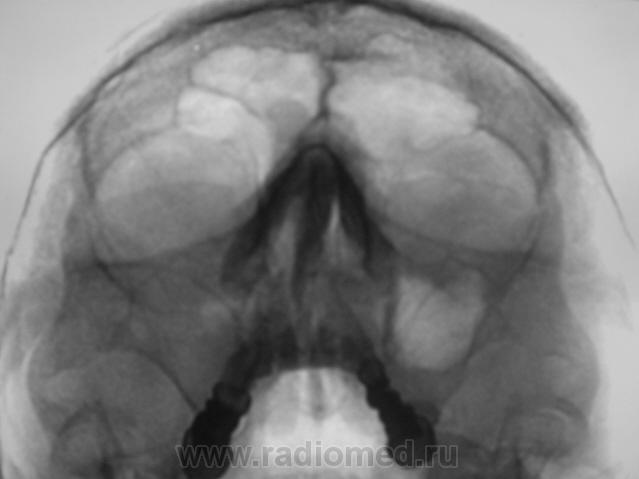

Пациент второй.

Второй случай. уровень слева,субтотальное затенение справа.киста правой половины лобной.....